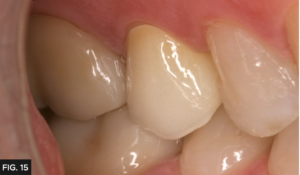

FINAL CEMENTATION

The final restoration (FIG. 15) required minimal adjustment before seating with RelyX™ Luting Plus (3M), a resin modified glass ionomer. This cement was chosen because the preparation had adequate retention and is preferred due to its easy clean up, predictable and long-term retention. Once seated, the cement is allowed to reach a gel stage, approximately 90 seconds, then excess is easily removed. This step can be expedited with tack curing. Had this preparation been a short crown or limited retention, a bonding sequence and resin cement (ie. RelyXTM Universal, 3M) would have been the preferred technique. The final restoration is shown in (FIG. 15).